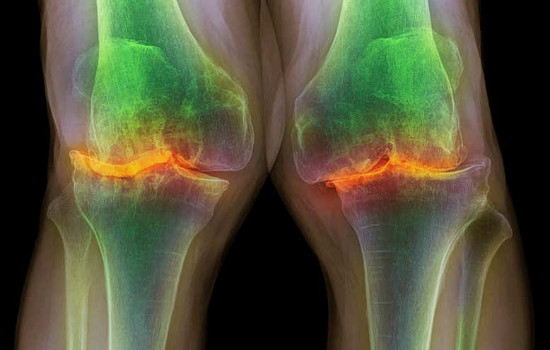

ossos | Foto: Reprodução

Radiografia dos joelhos de um homem de 87 anos com osteoartrite grave. (Foto: Reprodução)